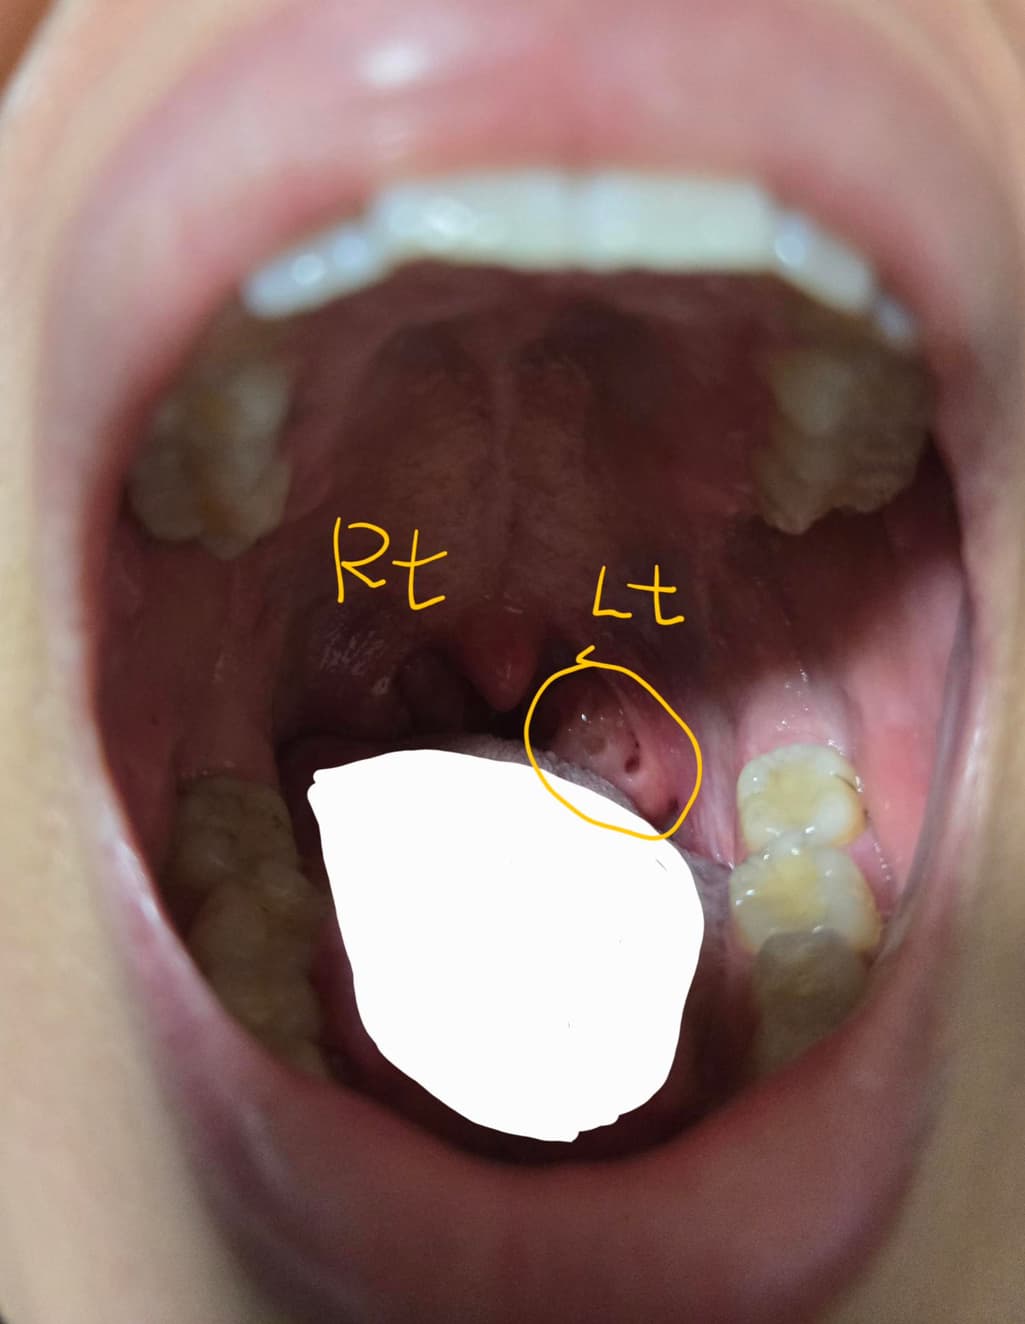

양쪽 모두그런것도 아니고 왼쪽만 그렇고

크기도 더 커진것인가 생각했는데 예전에 올린 글을 보니 조금 커진것 같거나 비슷한것 같더라구요.

현재 사진에서는 왼쪽 편도에 구멍이 있는 것으로 보입니다. 보통, 편도 소립이라고 불리우는 구멍인데 해부학적으로 구조가 달라서 한쪽에만 결석이 생기는 경우가 간혹 발생하기도 합니다. (따라서 원래 한쪽만 그렇다고 보기는 어렵습니다.)